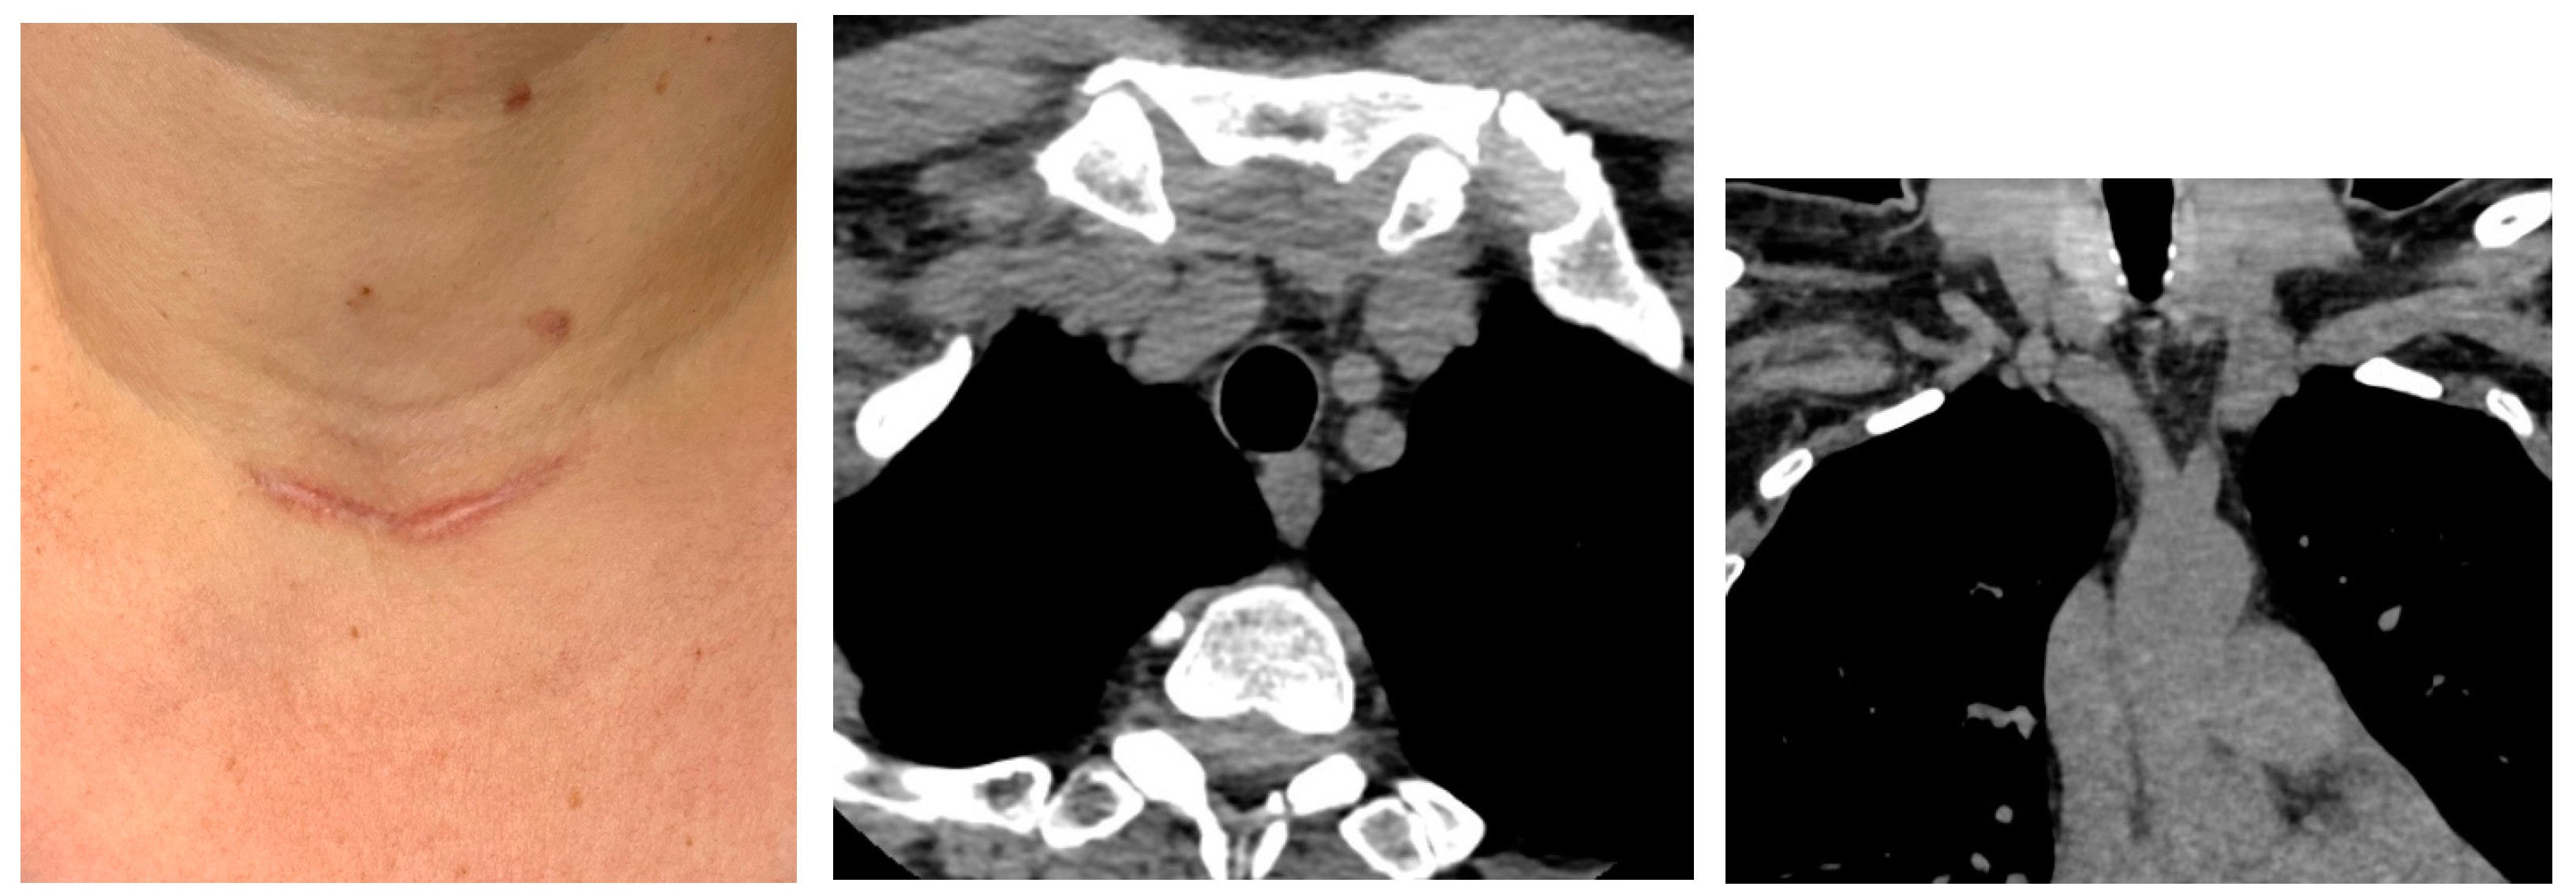

3.1.1. Baseline Admission: Identification of a Mediastinal Mass and an Adrenal Tumour Following Prior COVID-19 Infection

3.1.2. Endocrine and Imaging Investigations After One Year of Surveillance

3.2. Ectopic Mediastinal Thyroid Removal via Cervicotomy